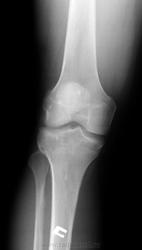

Пол пациента: Мужской пол Тип патологии: Травма Область исследования: Скелетно-мышечная система Методы исследования: Rg Травма, 50 лет, падение на колено, хирург искал перелом надколенника. Что за очаги оссификации? https://radiomed.ru/sites/default/files/styles/case_slider_image/public/user/17212/3.jpg?itok=ZOARUHOu https://radiomed.ru/sites/default/files/styles/case_slider_image/public/user/17212/4.2.jpg?itok=FzC0cneJ https://radiomed.ru/sites/default/files/styles/case_slider_image/public/user/17212/4.jpg?itok=jE1z60Rz ID:28343 Thu, 02/05/2013 - 13:17 #1 И.Бондаренко Offline Last seen: 13 hours 12 min ago Joined: 13.09.2011 - 22:55 Posts: 9206 Возможно обычная остеопойкилия. Thu, 02/05/2013 - 22:30 #2 Almo Offline Last seen: 18 hours 5 min ago Joined: 28.09.2008 - 18:50 Posts: 8259 +1.

Возможно обычная остеопойкилия.